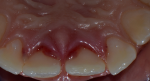

Clinical findings: the extraoral examination showed no other injuries of the lip or nose. Concerning the intraoral examination, the maxillary permanent central incisors appeared elongated with bleeding from the periodontal ligament. From a palatal and lateral view, it was observed that the crown of both central incisors was displaced to the palatal direction (Figure 1).

Figure 1: palatal clinical preoperative view of traumatized teeth